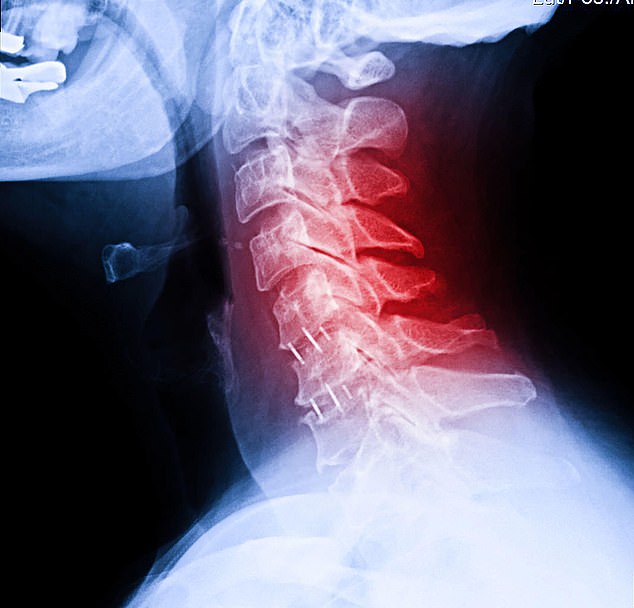

सिर और गर्दन का कैंसर मुंह, गले, वॉयस बॉक्स, नाक, साइनस और लार ग्रंथियों के कैंसर के लिए एक व्यापक शब्द है।

सिर और गर्दन को प्रभावित करने वाला कैंसर यूके में कैंसर का आठवां सबसे आम रूप है, हालांकि वे महिलाओं की तुलना में पुरुषों में दो से तीन गुना अधिक आम हैं।

कैंसर रिसर्च यूके के अनुसार, हर साल लगभग 12,500 नए मामलों का निदान किया जाता है, और घटनाएं बढ़ रही हैं।

मैकमिलन कैंसर सपोर्ट का कहना है कि 10 में से नौ सिर और गर्दन के कैंसर स्क्वैमस कोशिकाओं में शुरू होते हैं।

स्क्वैमस कोशिकाएं चपटी, त्वचा जैसी कोशिकाएं होती हैं जो मुंह, नाक, स्वरयंत्र, थायरॉयड और गले की परत को ढकती हैं।